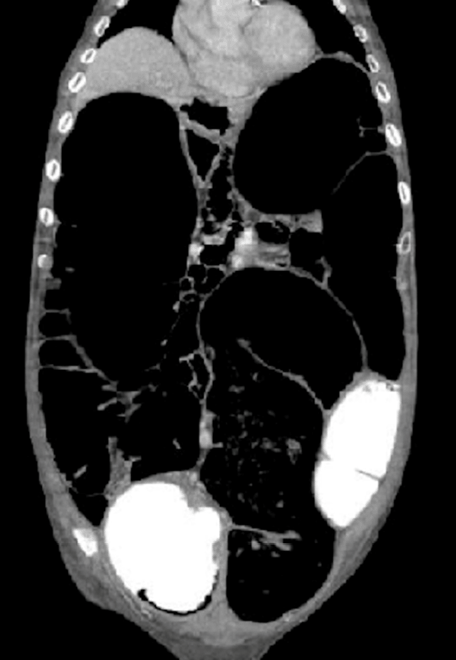

X-ray of the abdomen (erect and supine) showed the appearance of extensive colonic gaseous distention that raised both diaphragmatic leaflets. Colonic liquefied fecal content was seen extending down to the rectum. Overall impression on imaging was of pseudo-obstruction (Figure 1). Computed tomography (CT) scan of abdomen with contrast showed marked diffuse colonic dilation with no evidence of a mechanically obstructing lesion (Figure 3) And (Figure 4).

Figure 1: Supine abdominal X-ray on admission (Cecum approximately 9 cm).

Figure 4: Coronal abdominal computed tomography scan view showing dilated colon (ascending colon approximately 10 cm).